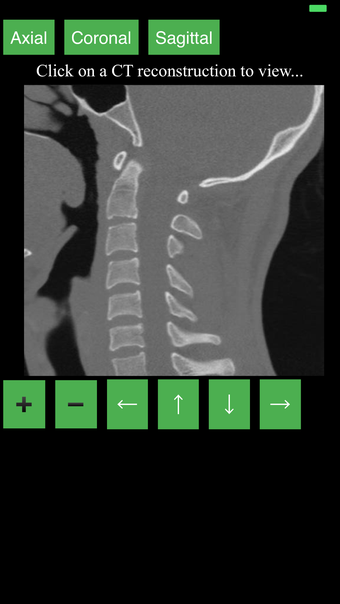

Перекрестные разрезы данных КТ предоставляют динамический и интерактивный метод просмотра поперечной анатомии человека. Вы можете вращать, увеличивать и перемещать изображение, чтобы изучать любую часть тела в деталях.

Перекрестные разрезы создаются с помощью комбинации математических алгоритмов для интерпретации данных из серии сканирований. Результирующие изображения затем преобразуются в серию 2D поперечных срезов и отображаются в специальном приложении для просмотра.